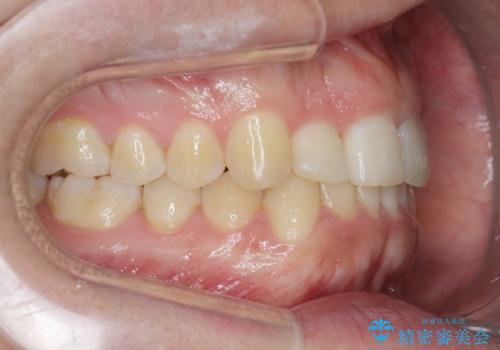

前歯が隠れていて見えない クロスバイトの矯正治療

- 「前歯が1本隠れていて見えない、歯並びを矯正治療で改善したい。」と希望され来院されました。

奥に隠れている前歯を並べられるスペースを確保したのち、歯並びを整えていきます。

前歯のスペース不足により1本だけ後方に位置している状態でしたが、しっかりとスペースを確保し配列することができました。